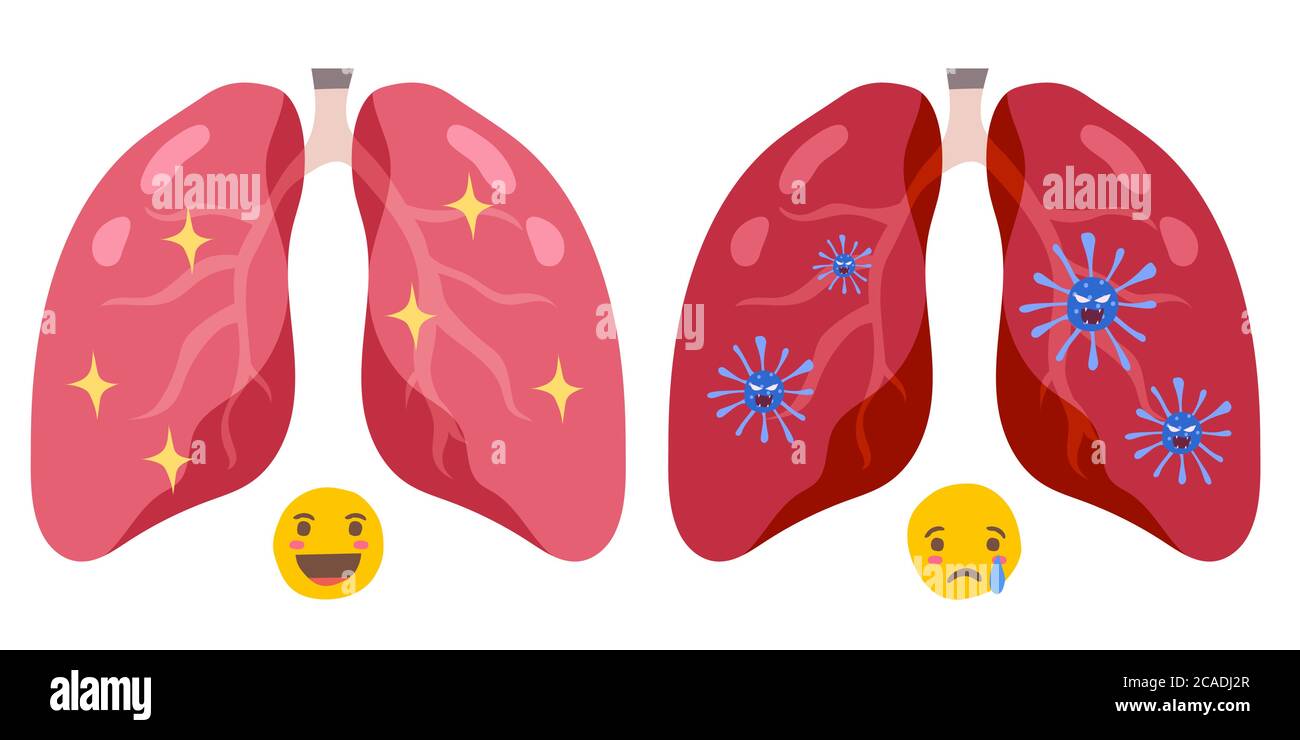

RF2CADJ2A–Segno infografica con Cartoon ha tosse, febbre, Gola irritata e freddo in Coronavirus o Covid-19 focolaio.